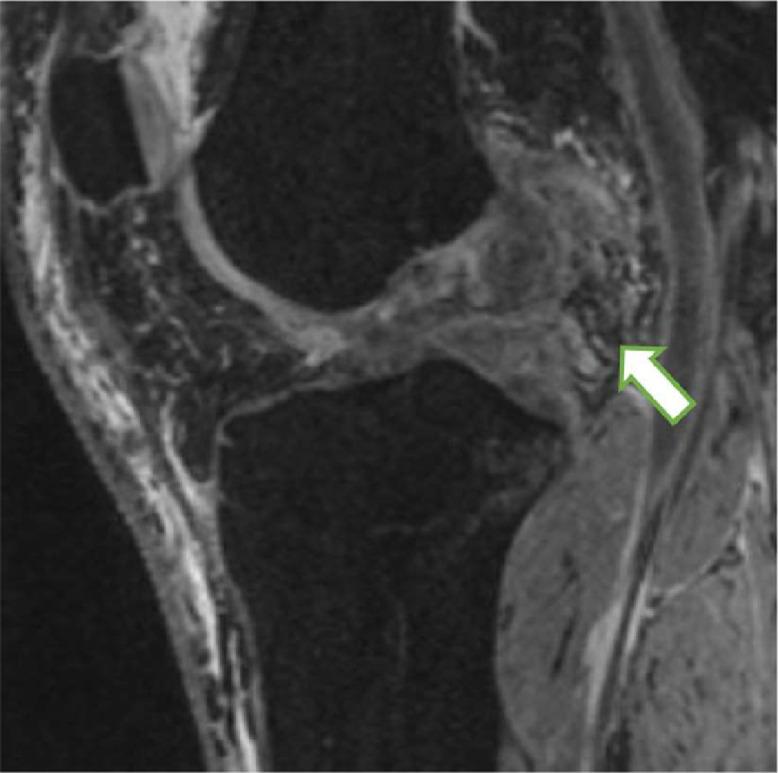

Traumatic dislocations of the knee can result in significant soft tissue damage including multiligamentous and meniscal knee injury. When a meniscal tear involves the posterior horn, the meniscus loses one of its attachments to the tibia and can become extruded from the joint. Stener-like lesions of the knee have been reported throughout the literature; however, they have been exclusively described as a distal tear of the medial collateral ligament (MCL) lying superficial to the pes anserine tendon which prevents anatomic healing. The purpose of this report is to present a previously unreported unique variant of a lateral meniscus tear in the setting of a MLKI. In this case presentation, the lateral meniscus became extruded superficial to the intact lateral collateral ligament (LCL) resulting in a Stener-like lesion. Corrective recognition of lesions like these and timely surgical intervention is recommended to restore native anatomy and prevent chronic pain, instability, and premature degenerative disease. Level IV, Case report.

膝关节创伤性脱位可导致严重的软组织损伤,包括膝关节多韧带和半月板损伤。当半月板撕裂累及后角时,半月板失去其与胫骨的一个附着点,可能会从关节中挤出。膝关节类似斯滕纳(Stener)病变在文献中已有报道;然而,它们仅被描述为位于鹅足肌腱浅面的内侧副韧带(MCL)远端撕裂,这会妨碍解剖学愈合。本报告的目的是介绍一种在多韧带膝关节损伤(MLKI)情况下外侧半月板撕裂的先前未报道的独特变异。在本病例报告中,外侧半月板在完整的外侧副韧带(LCL)浅面挤出,导致类似斯滕纳病变。建议正确识别此类病变并及时进行手术干预,以恢复正常解剖结构,预防慢性疼痛、不稳定和过早的退行性疾病。四级,病例报告。